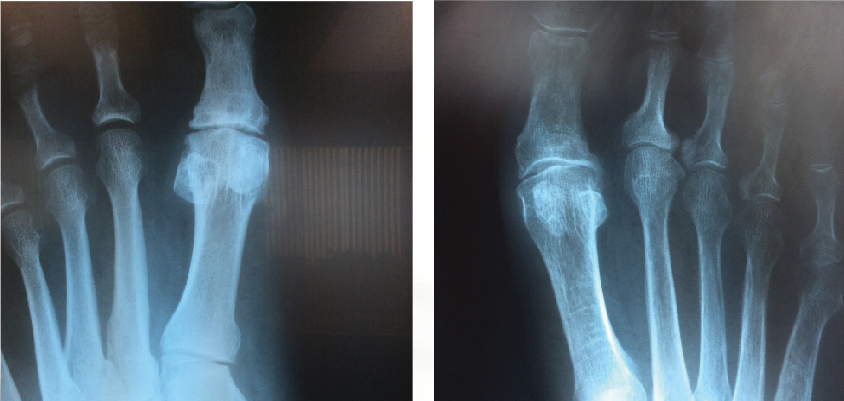

The symptoms of hallux rigidus include pain with range of motion of the first MPJ, swelling around this joint and pain with irritation from footwear.4 Physical examination reveals bone enlargement and restricted motion of the first MPJ.5 Radiographic findings of hallux rigidus include joint space narrowing of the first MPJ, osteophyte formation, subchondral sclerosis, flattening of the first metatarsal head, trumpeting of the base of the proximal phalanx and loose bodies.6,7

Many authors have connected metatarsus primus elevatus as a causative factor for hallux rigidus. Meyer reviewed radiographs of 120 patients and found that hallux rigidus findings did correlate with the presence of metatarsus primus elevatus.20 Roukis determined the mean first to second metatarsal elevation to be 5.8 mm in a hallux rigidus group, which was higher than in patients with other foot pathologies.21 Bouaicha and coworkers attempted to standardize techniques to measure alignment of the first metatarsal on lateral radiographs and found that elevation of the first metatarsal greater than 5 mm was predictive of hallux rigidus.17

The fact that hallux rigidus and metatarsus primus elevatus seem to go together when looking at lateral radiographs reaffirmed the long held notion that hypermobility and elevation of the first ray must be a primary cause of hallux rigidus. However, two studies have raised the question about whether such a cause-effect relationship really exists. Horton and coworkers studied radiographs of patients with and without hallux rigidus, and found no difference in alignment of the first ray between the two groups.18 In cases of severe hallux rigidus, the metatarsus primus elevatus increased significantly, suggesting to the authors that elevation of the first metatarsal occurs as a result of hallux rigidus and not vice versa.

Bouaicha and coworkers further studied the role of metatarsus primus elevatus and hallux rigidus.17 They observed that some of the conflicting results of previous studies of metatarsus primus elevatus were due to unreliable measurement techniques of radiographs taken of patients with hallux rigidus. Bouaicha and colleagues described a new measurement technique to measure elevation of the first metatarsal relative to the second metatarsal. With this technique, a correlation between metatarsus primus elevatus and hallux rigidus was present, but the authors could not determine the cause-effect relationship.